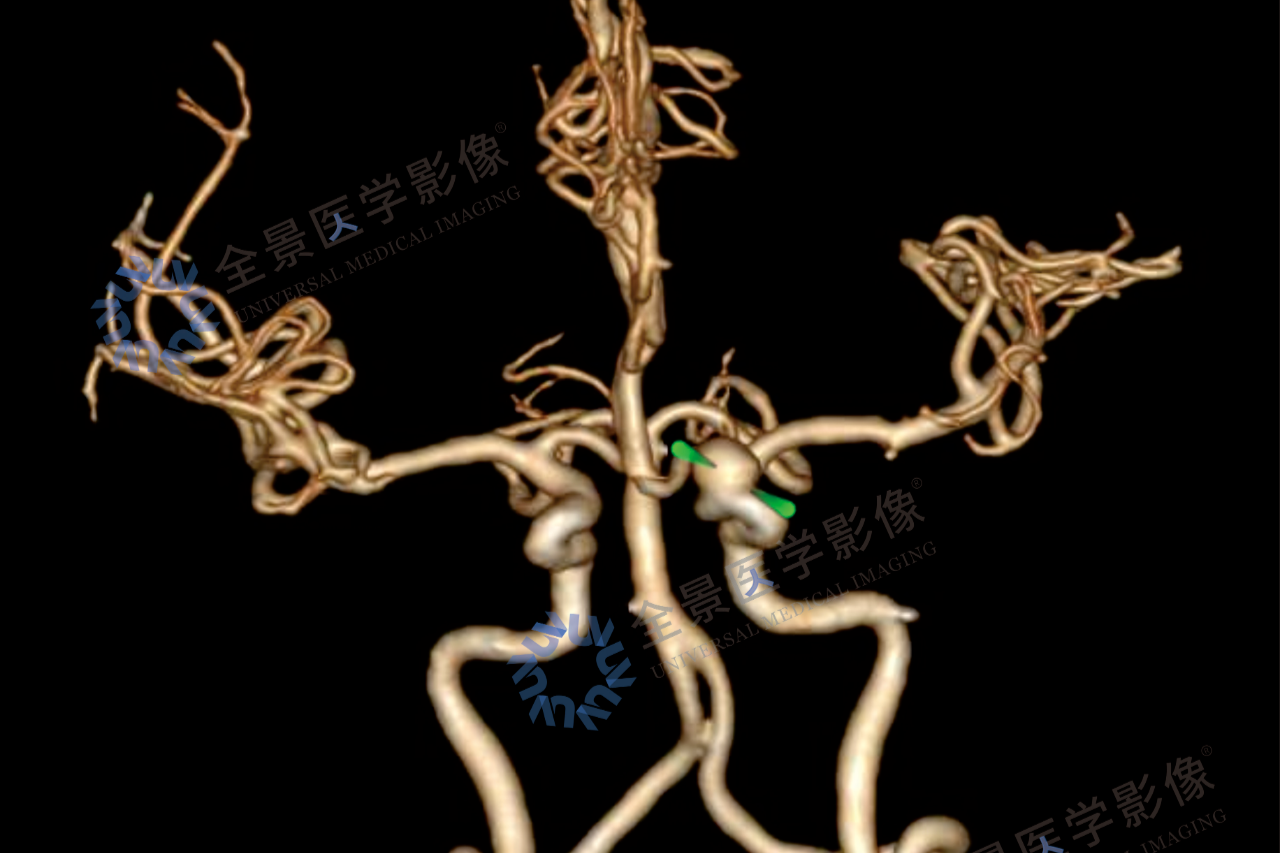

控糖不力,并发症悄然而至——影像学评估心、脑、肾、足风险